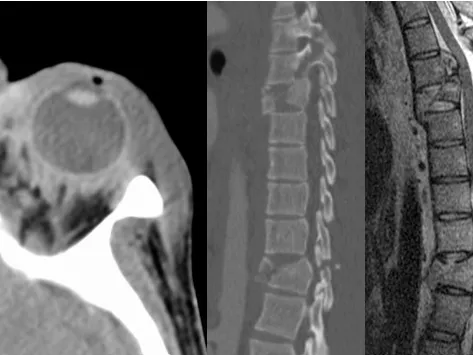

In this interactive, case-based fellowship course, you will develop key skills to confidently interpret head and spine imaging studies for trauma patients. You will learn to recognize various traumatic injury patterns, including those that may not be present in the acute setting. The training will enable you to identify life-threatening emergencies, distinguish between different types of spinal fractures (including pathological fractures), and differentiate traumatic from non-traumatic intracranial haemorrhages . Additionally, you will gain a deeper understanding of the limitations inherent in imaging studies, enhancing your ability to make more informed and accurate diagnoses.